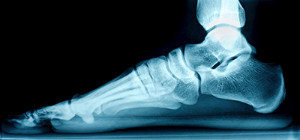

Flatfoot is a condition in which the arch of the foot is depressed and the sole of the foot is almost completely in contact with the ground. About 20-30% of the population generally has flat feet because their arches never formed during growth.

- Flat look to one or both feet